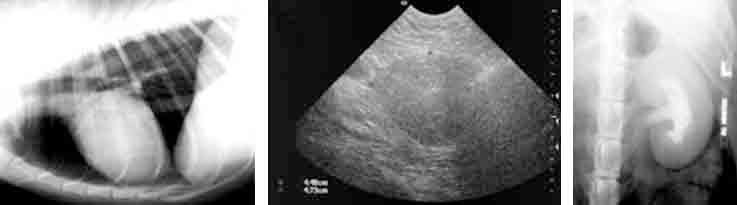

From left to right: Dog chest radiograph; image of dog prostate with benign prostatic hypertrophy; dog kidney with chronic infection.

Our comprehensive imaging capabilities allow evaluation of any organ or body system. In addition to the sophisticated cross sectional imaging modalities we have extensive experience in plain and contrast radiography and ultrasound, including endocavitory, evaluation. These modalities continue to have applications in the development of new therapeutic applications and we can help you to select the most appropriate and cost effective imaging method for your study. Morphometric measures can be made from the images and some measures of echogenicity can be made from ultrasound images.